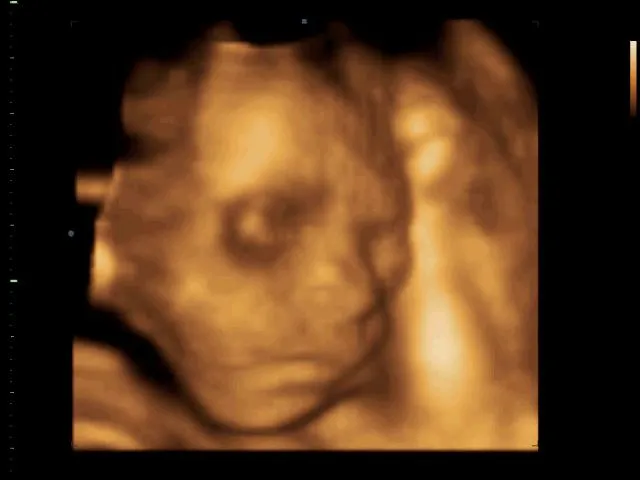

Ecografia 4d

ECOGRAFIA 4D - Poliambulatorio Valturio Rimini - Centro Medico ...